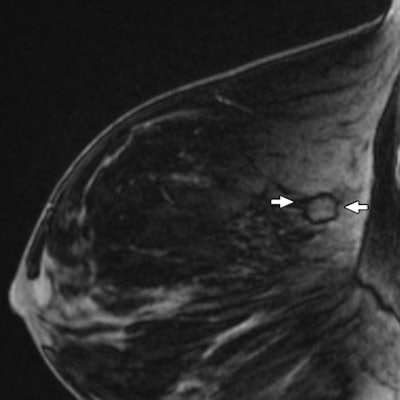

| Contrast-enhanced fat-suppressed T1-weighted sagittal MR image of right breast shows mildly enhancing mass (arrows) that corresponds to asymmetry. |